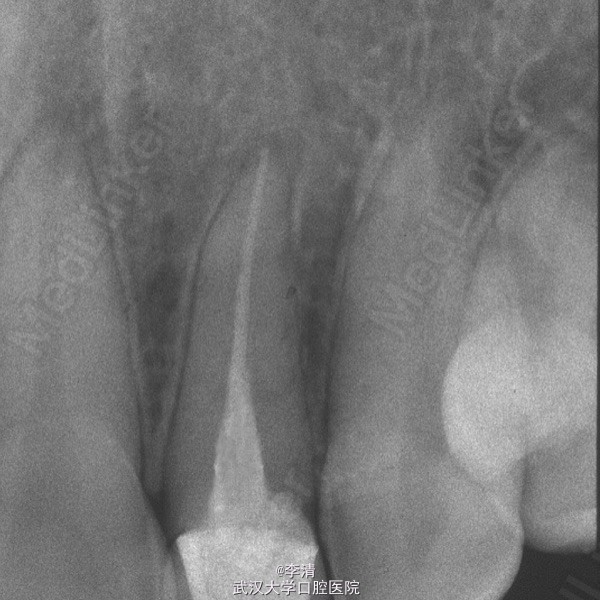

查体 辅查

X片示侧切牙行根管治疗,根尖无明显暗影

诊断 处理

侧切牙残根 行纤维桩,铝瓷全瓷冠修复